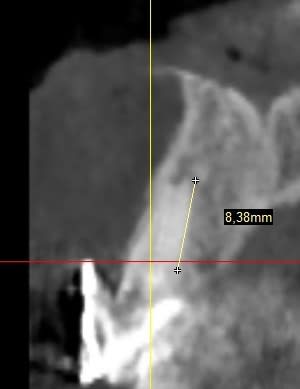

Je vous met la pano complète ainsi que des détails qui je l'espère seront suffisants pour vous faire une idée.

Les hauteurs que j'ai pu indiquer comporte aussi de la dentine infiltrée, pardonnez moi de le préciser.